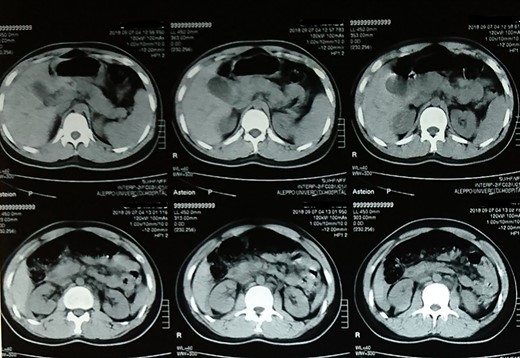

Follow-up computed tomography scan of the abdomen showing no abnormalities.

On the first day after surgery, the patient’s overall condition was stable. On the fourth day, the drainage tube was removed and a computed tomography scan of the abdomen was performed, which was normal (Fig. 2). Afterwards, the patient was discharged and did not report any further complaint.